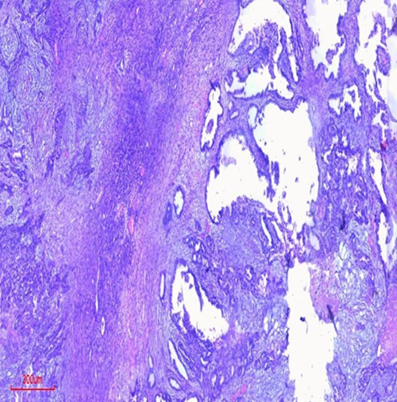

She had a staging laparotomy with total abdominal hysterectomy with bilateral salpingo-oophorectomy, infracolic omentectomy, and excision of the umbilical nodule on the fifth day of admission. The tissue specimen sent for histology reported ovarian tissue with a distorted architecture due to proliferating malignant epithelial cells forming glandular to cystic structures as well as papillary structures and compact nests. The individual malignant cells are pleomorphic with round to oval nuclei and moderate eosinophilic cytoplasm. There are extensive areas of necrosis. The histology diagnosis was that of a bilateral low-grade serous papillary cystadenocarcinoma with metastases to the umbilicus and omentum. Immunohistochemistry for p53 protein was negative (Figure 2-5).

Figure 3. Ovarian tissue with low-grade serous papillary cystadenocarcinoma (H&E, x20).